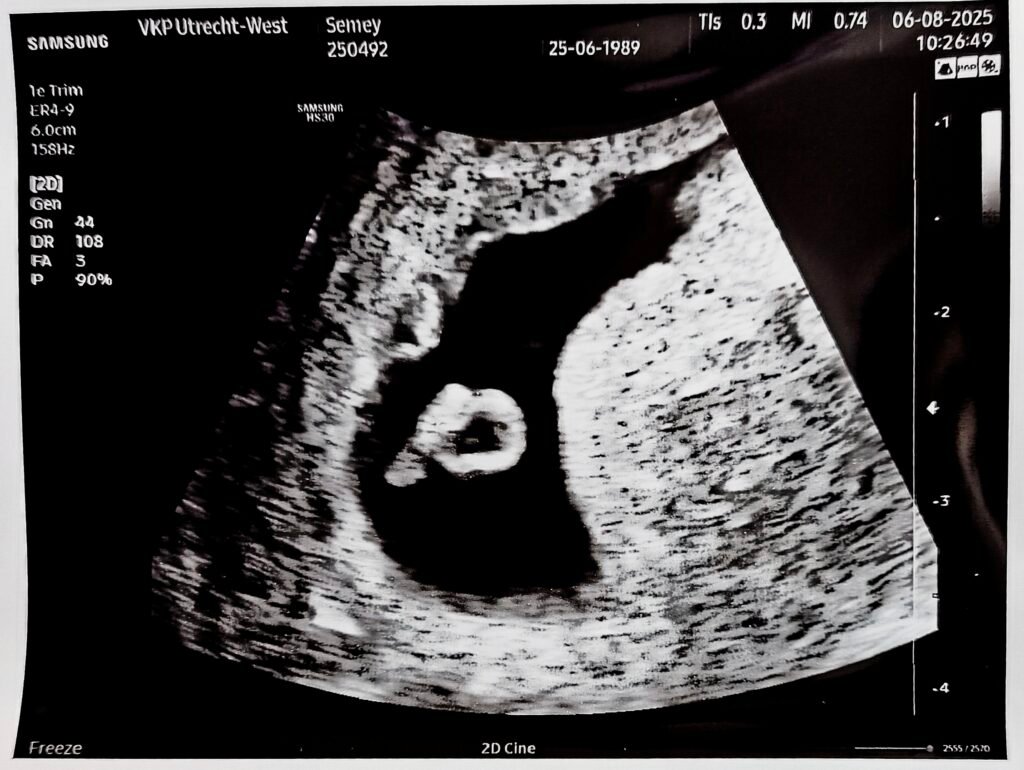

First Echo

19/07/2025

In the middle of this clump of cells, you can see the baby upside down on the left side in the middle of the uterus.

That big circular shape attached to the baby is just the yolk sack (they said).

They showed us for the first time a couple of flickering pixels in a screen, and we were told that that was their heart. Tessa pretended she could see something. Alberto actually did.